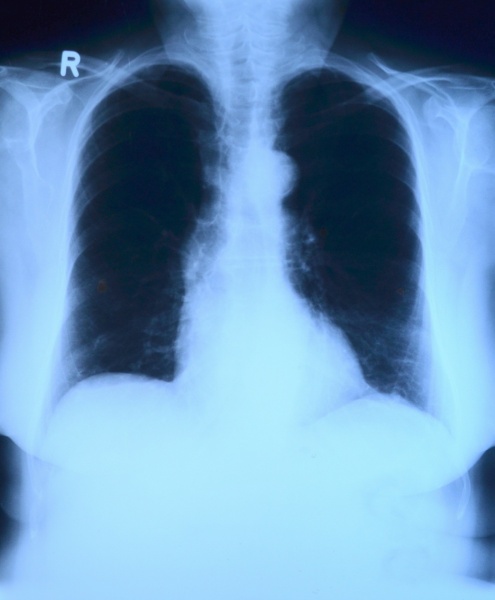

Płuca większości osób, które wyzdrowiały z COVID-19, dobrze się regenerują - informują naukowcy na łamach “Clinical Infectious Diseases”. Poniżej najnowsze doniesienia dotyczące węchu i smaku, a także znaczenia otyłości w przebiegu COViD-19.

Badanie prowadzone przez doktora Brama van den Borsta, pulmonologa z centrum medycznego Radboud University w Nijmegen (Holandia), objęło 124 pacjentów. Osoby te wyleczyły się z ostrych zakażeń COVID-19 i były objęte opieką poszpitalną w poliklinice centrum medycznego w Dekkerswald nazwanej Corona Aftercare. Pacjenci, którzy zostali przyjęci do centrum medycznego uniwersytetu Radboud z powodu COVID-19, otrzymują zaproszenie z Corona Aftercare. Także osoby, które przeszły przez COVID-19 w domu i nadal mają objawy, mogą otrzymać skierowanie od lekarza rodzinnego.

Pacjenci byli badani za pomocą tomografii komputerowej, wykonywano u nich testy czynnościowe płuc i inne czynności diagnostyczne. Analizując wyniki po trzech miesiącach naukowcy wykazali, że tkanka płucna pacjentów dobrze się regeneruje. Resztkowe uszkodzenie tkanki płucnej było na ogół ograniczone i najczęściej obserwowano je u pacjentów leczonych na oddziale intensywnej terapii.

Najczęstsze dolegliwości utrzymujące się po trzech miesiącach to zmęczenie, duszność i bóle w klatce piersiowej. Wiele osób nadal doświadcza ograniczeń w swoim codziennym życiu, a także obniżonej jakości życia. Jak wyjaśnia Bram van den Borst: „Wzorce, które obserwujemy u tych pacjentów, wykazują podobieństwo do wyzdrowienia po ostrym zapaleniu płuc lub zespole ostrej niewydolności oddechowej (ARDS), w którym płyn gromadzi się w płucach. To bardzo budujące gdy widzę, że płuca po zakażeniach COVID-19 wykazują ten poziom regeneracji”.